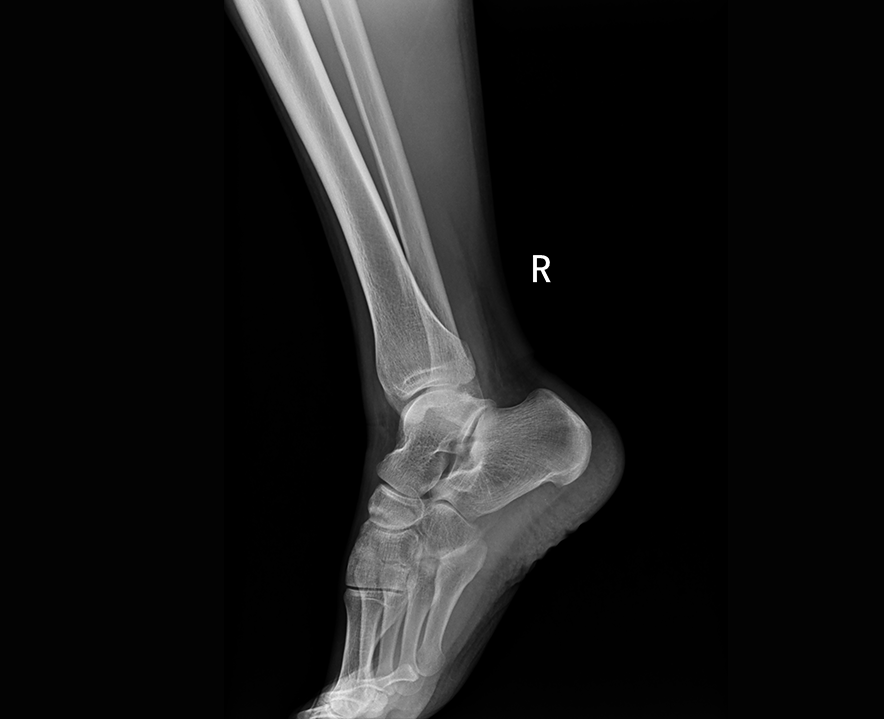

自主研发高频逆变高压发生器,配合高效自主增强图像处理技术,呈现清晰细腻的图像效果。

临床图像